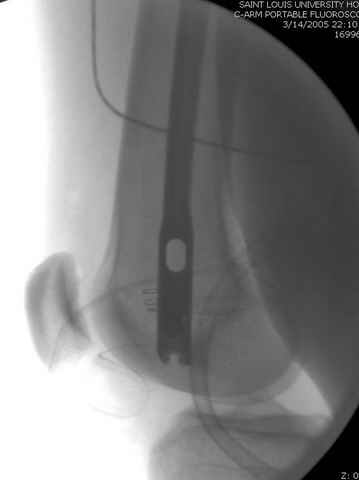

По поводу открытого перелома больной ургентно взят на ретроградное интрамедулярное штифтование, после рутинного дебрайдмента и фасциотомии на бедре и на голени.

перелом бедра

интраоперационные